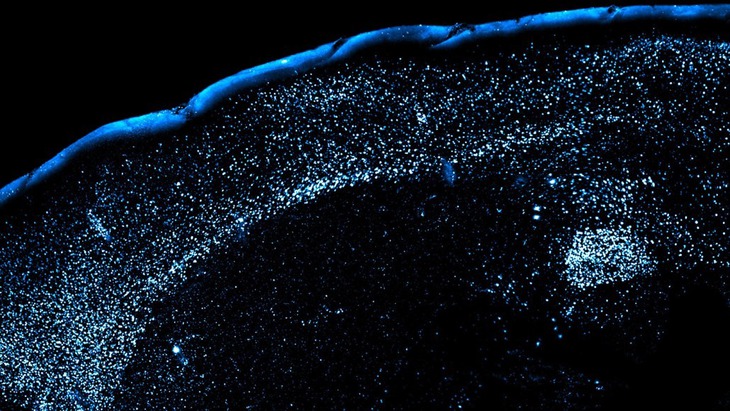

Neurons in a region of the brain called the amygdala light up (blue) when the body encounters a strange and unpleasant food. The same neurons are then enhanced to help the brain remember, and avoid, unpleasant tastes in the future - Photo: Princeton University